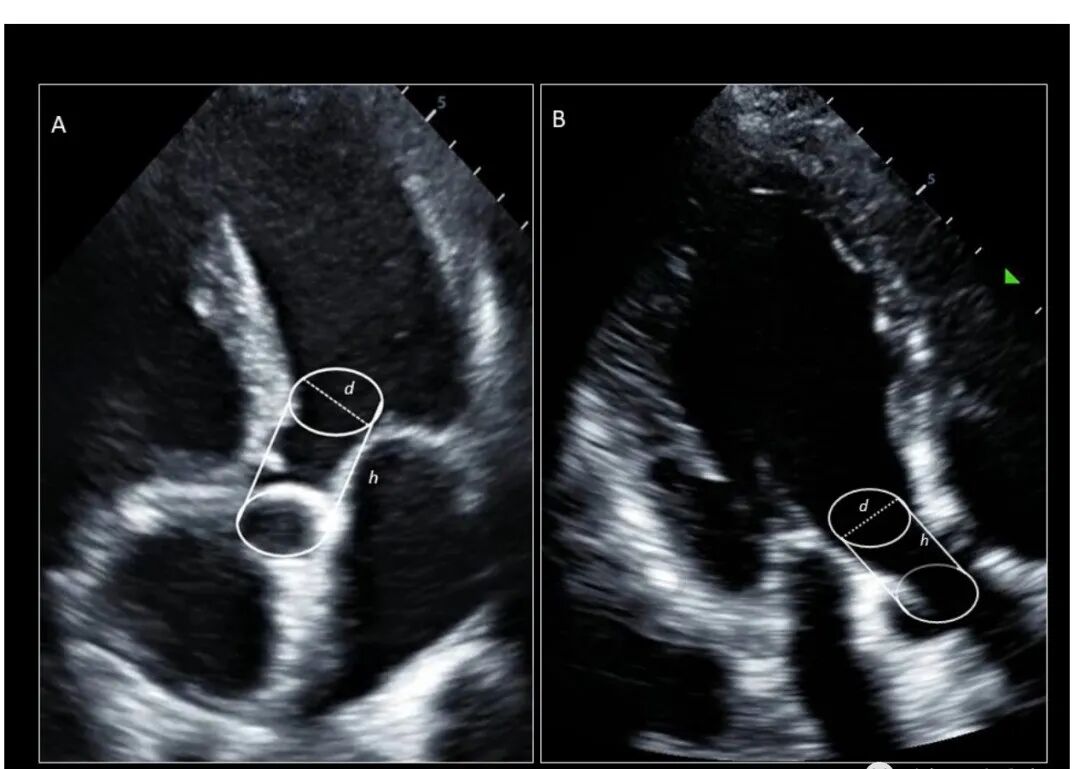

在收缩期从左心室射出的血量通过形状像圆柱体的左心室流出道 (LVOT)。因此,求解该圆柱体的体积会产生 SV(图 1):

图 1. 在心尖 5 腔 (A) 和心尖 3 腔 (B) 视图中将 LVOT 可视化为圆柱体。

圆柱体体积 = 高度 × 横截面积

圆柱体的高度是 LVOT VTI,通过在心尖 5 腔或 3 腔视图中放置在主动脉瓣 (AV) 近端的脉冲波 (PW) 多普勒获得。横截面积 (CSA) 源自 LVOT 直径,使用: